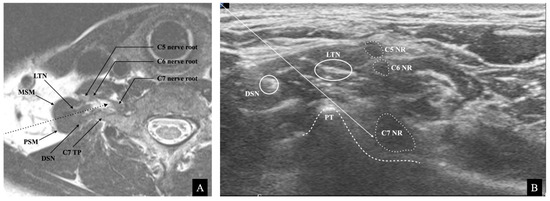

2.1. Ultrasound Image

indicates that it was outside the risk area in the simulated risk analysis. The LTN’s mean location and locational area estimated by the mean ± standard deviation (SD) are presented. The painted area indicates that the needle’s trajectory is expected to be associated with a high risk of LTN injury.